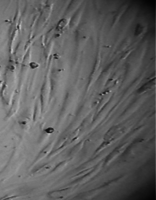

8 серия экспериментов. На дно культуральных чашек помещали образец исследуемого материала (фрагмент стержня из титана - диск диаметром 3 мм, толщиной 2 мм и массой 65 мг), после чего высевали фибробласты в концентрации 20000 клеток/смІ.

Наблюдение через сутки показало, что фибробласты пристают к дну культуральной чашки преимущественно вблизи образцов, при этом тела клеток располагаются вдоль периметра исследуемых дисков (рис. 38).

В отдаленных зонах фибробласты образуют редкий равномерный монослой, плотность которого в последующие сроки увеличивается с обычной для данной культуры скоростью, поэтому к концу наблюдения плотность насыщения не достигается.

Со вторых суток вблизи образцов фибробласты образуют второй слой клеток, а на четвертые сутки мы видим вокруг них такой же «валик», который мы наблюдали в 5 серии экспериментов (табл. 16).